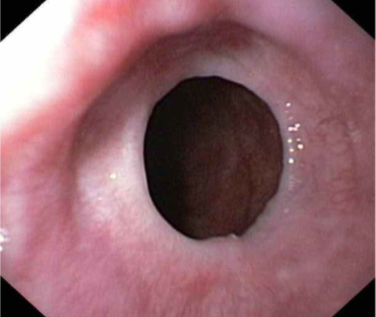

Eosinophilic Esophagitis

eosinophilic microabscesses

Adults: Dysphagia, odynophagia

Children: feeding intolerance

due to food allergy

most often in Atopic individuals (atopic dermatitis, allergic rhinitis, asthma, eosinophilia)

Concentric rings (trachealization)

Morphology: large numbers of eosinophils or eosinophilic microabscesses in epithelium